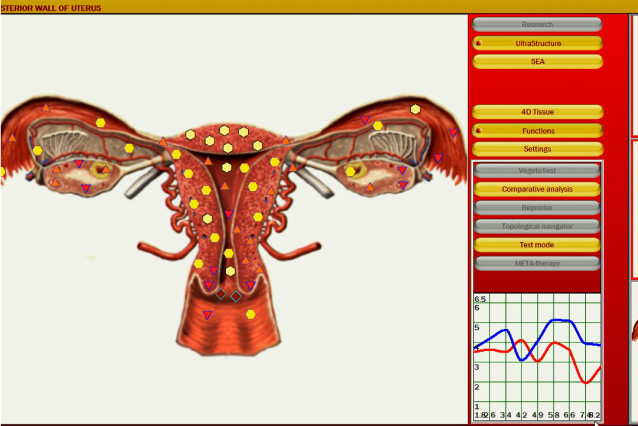

全身の各器官を状態によって6段階で評価します。

筋肉、肝臓、心臓、脳などの臓器はもちろんのこと、もう少し細かい細胞や神経、血管まで測定が可能です。

上図のように各組織ごとに評価し、数値として可視化されます。